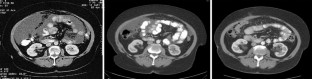

Fig. 2